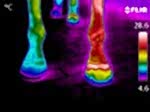

Equine thermography is better known as 'thermal imaging of horses'. It is a gentle, non-invasive method used to identify areas of injury or stress that would otherwise go unchecked.

Thermographic imaging of horses is intended as a preventative measure to aid diagnosis, rather than full diagnosis or treatment. Thermal imaging provides high definition images which will pinpoint any areas of pain or discomfort so your delegated professional can advise a relevant course of treatment. Having a thermal image taken of your horse can help you identify potential health issues sooner and as a result will ensure that your horse receives treatment quicker and will increase recovery time.

•  Farriery and Hoof Health i.e. abscess, bruising, laminitis, imbalanced trimming/ shoeing/ loading.

•  Lameness Localisation i.e. detection of changes in circulation or nervous system function.